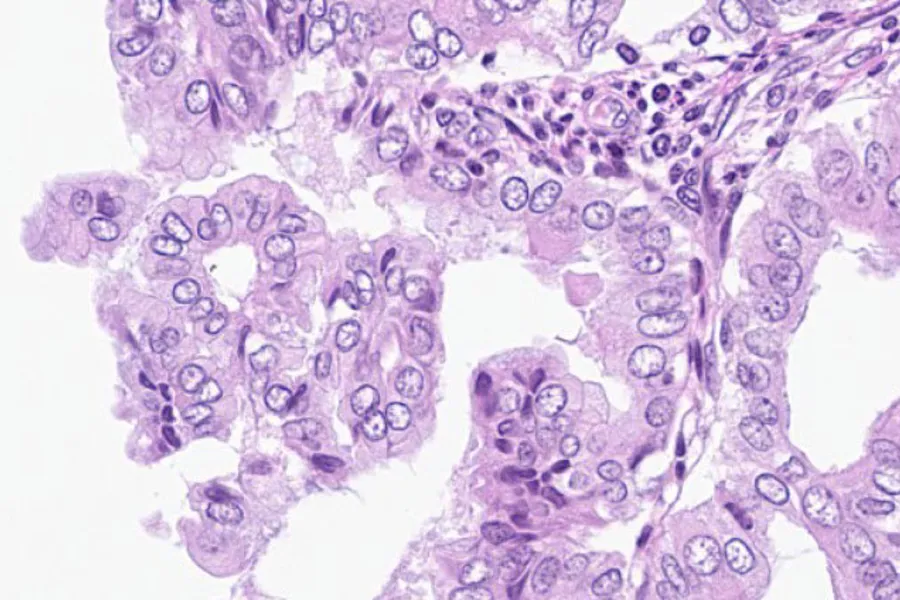

The figure above shows the APP workflow for risk classification of endometrial hyperplasia. A) Detection of endometrial tissue B) Labelling of endometrial structures including epithelial glands (green), lumen (yellow) and surrounding stroma (blue) C) Heatmap to identify the most dense region of glands D) Labelling of gland nuclei.